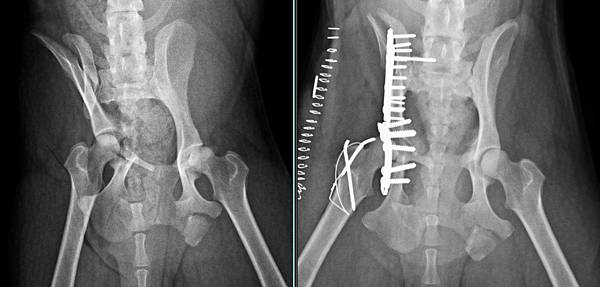

檢查發現骨盆多處骨折

2016-01-27 17.34.18.jpg

經過醫療團隊努力一一修復